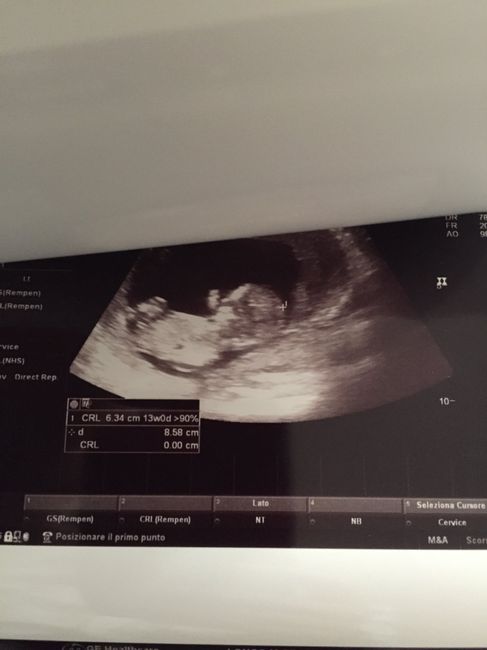

Ragazze mi unisco al gruppo anche io. Datemi la vostra opinione. Secondo voi è possibile sia femmina come mi dicono (tranne la gine che non si è voluta pronunciare).

Nub theory 1

Nub theory 2